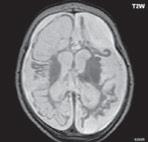

I.1.10 Hemimegaencefalie (hemimakrocefalie)

Způsobená nadměrným růstem části nebo celé mozkové hemisféry, nadprodukcí tvorby neuronů, poruchou migrace, buněčné organizace. Mozková kůra je zesílena, bývá doprovázená dysplazií kortexu, mívá poruchu v laminární organizaci, rovněž centrální šeď je zmnožena, je patrné rozšíření postranní mozkové komory, heterotopie šedé hmoty mozkové…

Zobrazení

CT i MR zobrazí zvětšenou hemisféru, rozšířenou postranní komoru, kalcifikace v bílé hmotě mozkové. V modalitě MR je patrné zesílení mozkové kůry, atypické gyrifikace, nodulární heterotopie, variabilní signál v T2W obrazu charakterizující sníženou myelinizaci, kalcifikace a gliózu, typické je postižení okcipitálního laloku.

Diagnostika a klinické příznaky

Nemocní mívají těžko kompenzovatelné epileptické záchvaty, progredující hemiparézy… Nadějné je včasné operační odstranění postižené hemisféry nebo její části.

Obr. I.1.10a Hemimegaencefalie, zvětšení pravé hemisféry, rozšíření pravé postranní komory, rozšíření mozkové kůry v oblasti pravé hemisféry

Obr. I.1.10b Hemimegaencefalie, zvětšení pravé hemisféry, rozšíření pravé postranní komory, rozšíření mozkové kůry v oblasti pravé hemisféry; stejný pacient jako na obr I 10a

Obr. I.1.10c Hemimegaencefalie, zvětšení pravé hemisféry, rozšíření pravé postranní komory, rozšíření mozkové kůry v oblasti pravé hemisféry stejný pacient jako na obr I 1 10a, b